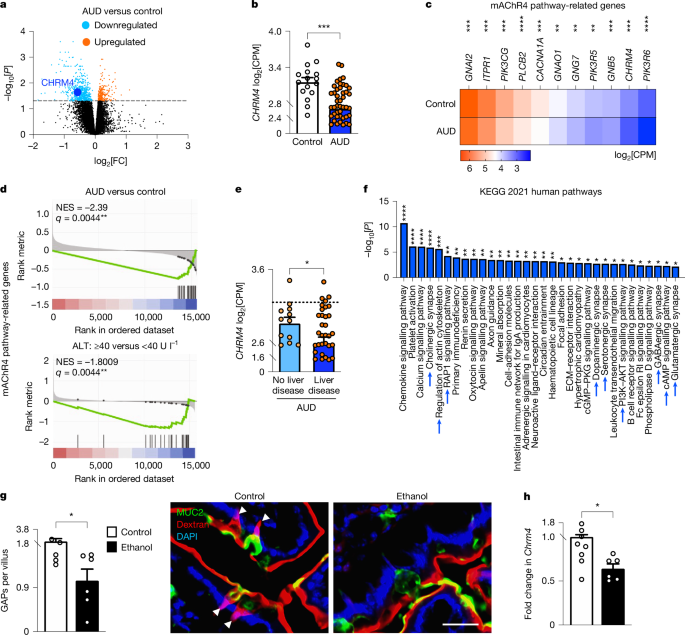

Alcohol Disrupts mAChR4-GAP-Mediated Barrier Function. Chronic alcohol exposure in both humans and mice downregulates mAChR4 expression and related pathway transcripts, leading to reduced GAP formation. mAChR4 downregulation strongly correlates with ALD progression in patients with AUD. Our preclinical models demonstrate that GAP closure is mediated through MAPK. This impairs barrier function by disrupting antigen sampling by LP-APCs, weakening antimicrobial immunity (REG3), and facilitating pathogenic bacterial translocation, a key driver of ALD progression.

Alcohol reduces mAChR4 and GAP formation. Figure from Llorente et al., Nature, 2025

GAP-Induced Immune Cascade Restores Protection. We define a novel and critical molecular mechanism involving GAP generation, which samples luminal antigens and initiates a protective, APC-mediated immune response. APCs secrete IL-23, promoting IL-22 production by ILC3s. IL-22 then acts on IECs and Paneth cells to induce antimicrobial Reg3 lectins. In summary, the GAPs → LP-APCs → IL-23 → ILC3s → IL-22 → Reg3 axis limits mucosa-associated bacteria, prevents bacterial translocation to the liver, and protects against ethanol-induced liver injury.

Intestinal IL6ST-Induced GAP Formation. Using genetic models with IEC-specific IL6ST activity either increased (gain-of-function) or decreased (loss-of-function), combined with a sophisticated co-culture system of small intestinal organoids and enteric neurons, we demonstrate that IL6ST/gp130 signaling promotes GAP formation through activation of the mAChR4 pathway.

Co-cultured mouse SI organoids with enteric neurons. Figure from Llorente et al., Nature, 2025 - mAChR4 Pathway Induction Prevents ALD. Activating mAChR4, chemogenetically, or via IL6ST signaling, restores this immune cascade circuit, reduces bacterial translocation, and prevents ethanol-induced steatohepatitis.

Selective AChR4 Positive Allosteric Modulation (AChR4 PAM), a promising therapy for ALD. Restoring GAP formation with an mAChR4 PAM prevents microbial translocation and ethanol-induced steatohepatitis in both WT and IEC-specific gp130-deficient mice, where disease is worsened.